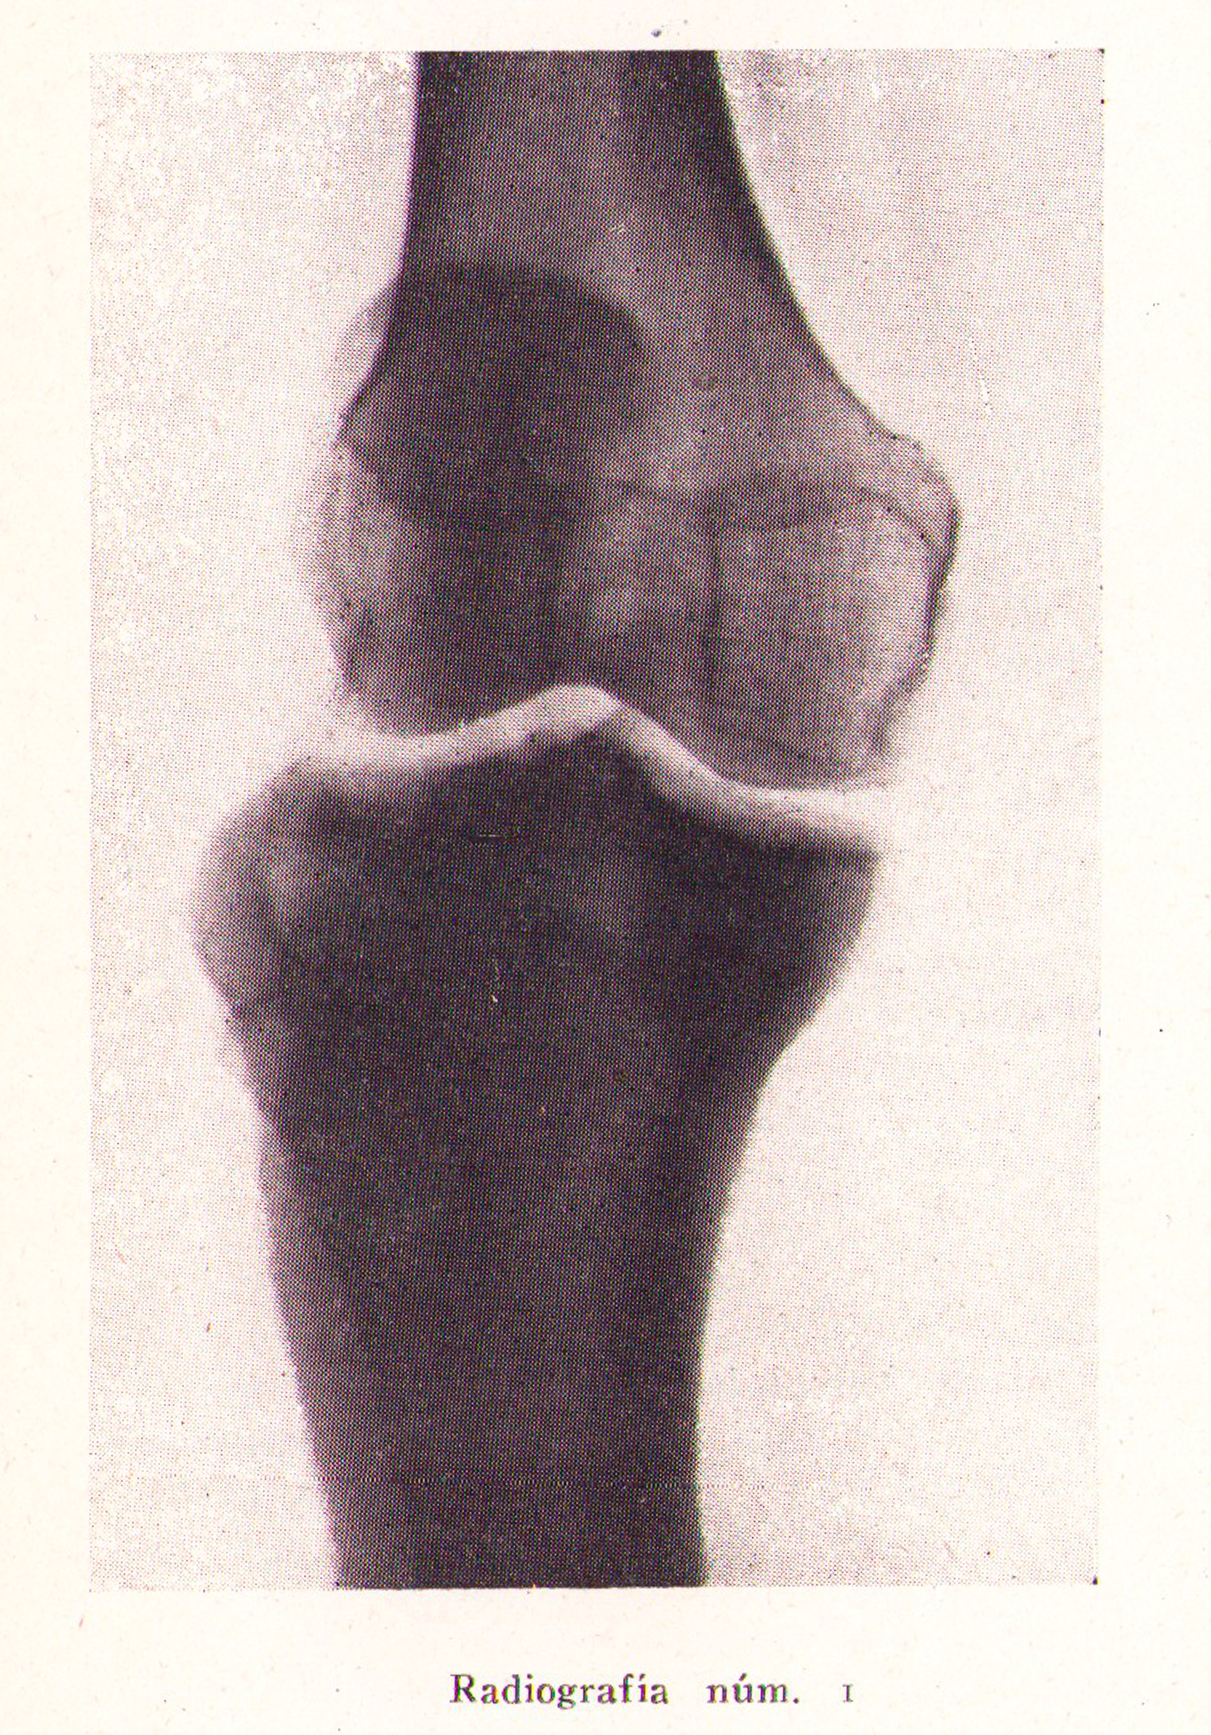

Radiografía, osteitis deformante de Paget

Revista Española de ciencias médicas, Clínica y laboratorio, Tomo XXXV, 1943